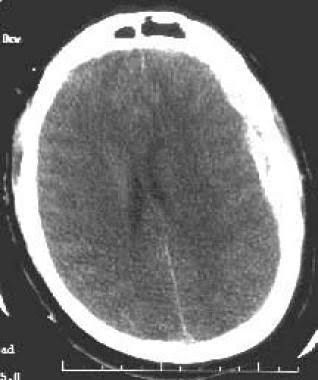

A craniotomy is the main treatment for subdural haematomas that develop soon after a severe head injury (acute subdural haematomas). During the procedure, the surgeon creates a temporary flap in the skull. The haematoma is gently removed using suction and irrigation, where it's washed away with fluid.